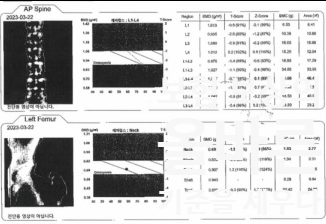

골다공증 검사결과 상에는

골다공증은 아니지만

골감소증으로 볼 수 있을 정도의 수치를 보였으나

이것이 사고관여도를 제한할만한 정도는 아니라고 생각하였고,

그에 대한 의견도 함께 제출하였습니다.

골다공증 검사 결과에 대하여 이견이 있었으나,

사고관여도 제한 없이 보험금이 지급 되었습니다